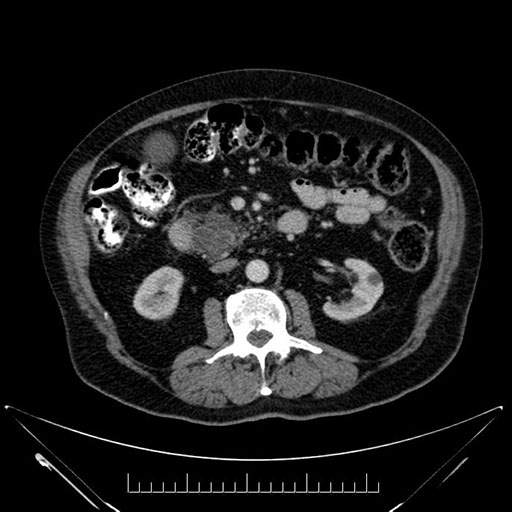

Coronal - stented